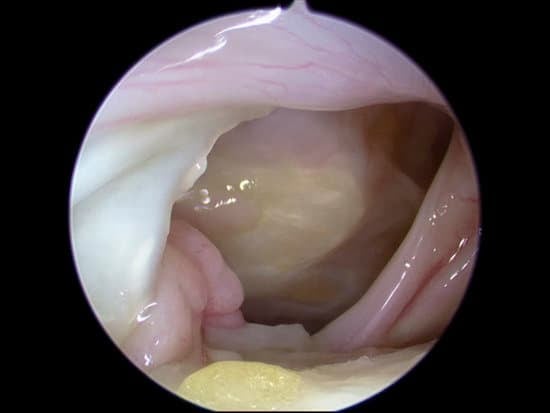

2. 수술 방법

손상된 상완이두근의 긴갈래힘줄을 원래 위치(견갑골 관절와순)에서 분리

견봉하 공간이나 상완골 결절 부위에 앵커나 나사못을 이용해 단단히 고정

불필요한 마찰과 통증을 줄이고, 이두근 모양 및 기능을 보존